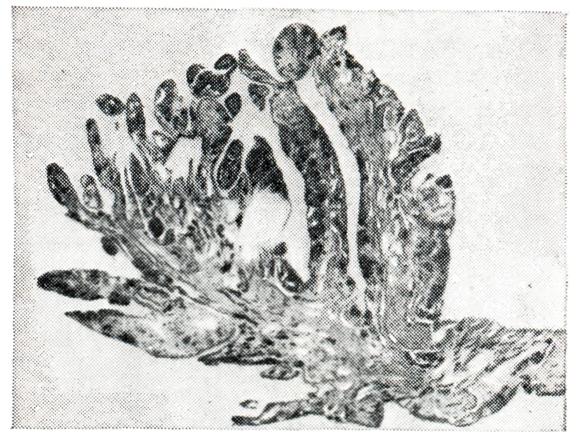

Рис. 1. | ||

В синовиальной оболочке наряду с гиперемией и отеком микроскопически обнаруживают пролиферацию и десквамацию покровных синовиоцитов, гипертрофию ворсин (рис. 1), пленки фибрина на поверхности, очаги фибриноидного набухания, диффузные инфильтраты, преимущественно из лимфо-гистиоцитарных элементов и единичных плазматических клеток. Наблюдается также разволокнение и фибриноидное набухание стенок мелких артерий и вен не только синовиальной оболочки, но и капсулы сустава и периартикулярных тканей. В воспалительный процесс вовлекаются нервы и чувствительные нервные окончания, что обусловливает резкую болезненность сустава. Суставной хрящ микроскопически не изменен. Может быть остеопороз эпифизарных отделов костей.